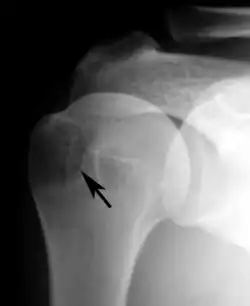

Shoulder impingement syndrome. Frontal X-ray of left shoulder.

Plain x-rays of the shoulder can be used to detect some joint pathology and variations in the bones, including acromioclavicular arthritis, variations in the acromion, and calcification. However, x-rays do not allow visualization of soft tissue and thus hold a low diagnostic value.[2] Ultrasonography, arthrography and MRI can be used to detect rotator cuff muscle pathology. MRI is the best imaging test prior to arthroscopic surgery.[2] Due to lack of understanding of the pathoaetiology, and lack of diagnostic accuracy in the assessment process by many physicians,[21] several opinions are recommended before intervention.

proximal humeral pseudocyst

Plain x-rays of the shoulder may show a “proximal humeral pseudocyst”. This localized area of bone atrophy is the result of increased blood circulation which demineralizes the bone at the attachment of the rotator cuff tendon. It is evidence of chronic inflammation of the rotator cuff. Chronic shoulder inflammation is frequently asymptomatic, and this cystic appearance may be the only evidence of an inflammation.[22][23]